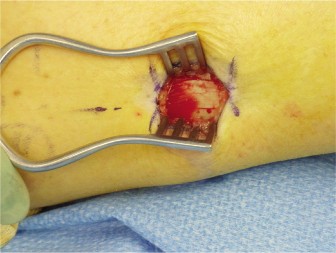

A 44-year-old, right-hand-dominant male with well-controlled diabetes and hypertension presents to clinic wit…